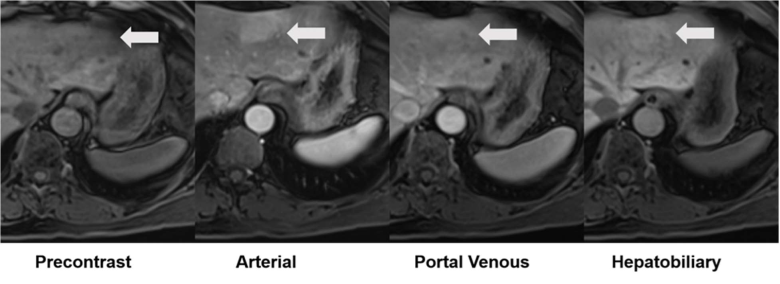

54-year-old with pathologically confirmed inflammatory adenoma in left lobe that underwent evaluation by gadoxetate disodium-enhanced MRI. Axial T1-weighted fat-saturated precontrast image shows isointensity to liver of adenoma (arrow). Axial arterial-phase postcontrast image shows hyperintensity to liver (arrow). Axial portal-venous phase postcontrast image shows hyperintensity to liver (arrow). Axial hepatobiliary-phase postcontrast image shows hyperintensity to liver (arrow). Hepatobiliary-phase liver-to-lesion contrast enhancement ratio is greater than zero, indicating true contrast material retention.

Ultimately, H-HCAs showed homogeneous/diffuse intralesional steatosis in 94% of the cohort. I-HCAs showed atoll sign in 58% and moderate T2-hyperintensity in 58%. Meanwhile, β-HCAs and βI-HCAs occurred in men in 63%, had mean size of 10.1 cm, and showed fluid components in 60% and hepatobiliary-phase iso- or hyperintensity in 80%. The SH-HCA subtype lacked distinguishing characteristics.